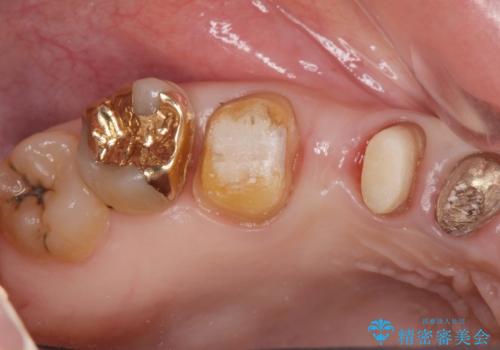

歯周ポケットの除去を併用したセラミック治療

- 歯周病や虫歯、歯の欠けなど多数の問題を他院で指摘され、今後長く持つように歯の問題をしっかりと解決したい。と希望され来院されました。

適合や審美性に優れるセラミック治療を行う前に、歯周病の問題を歯周外科を行うことで解決し将来的に不安のないような口腔内環境を整備していきます。

治療前に4-5mm程度あった歯周ポケットは全て2mm以内となり、非常に清掃性が高く、歯周病の再発しずらい環境に整えた上でのセラミック治療を実践することができました。